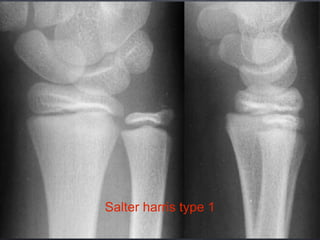

Classification

Salter harris classification

Salter harris type 1

Salter harris type 2

Salter harris type 3

Salter harris type 4

Salter harris type 5